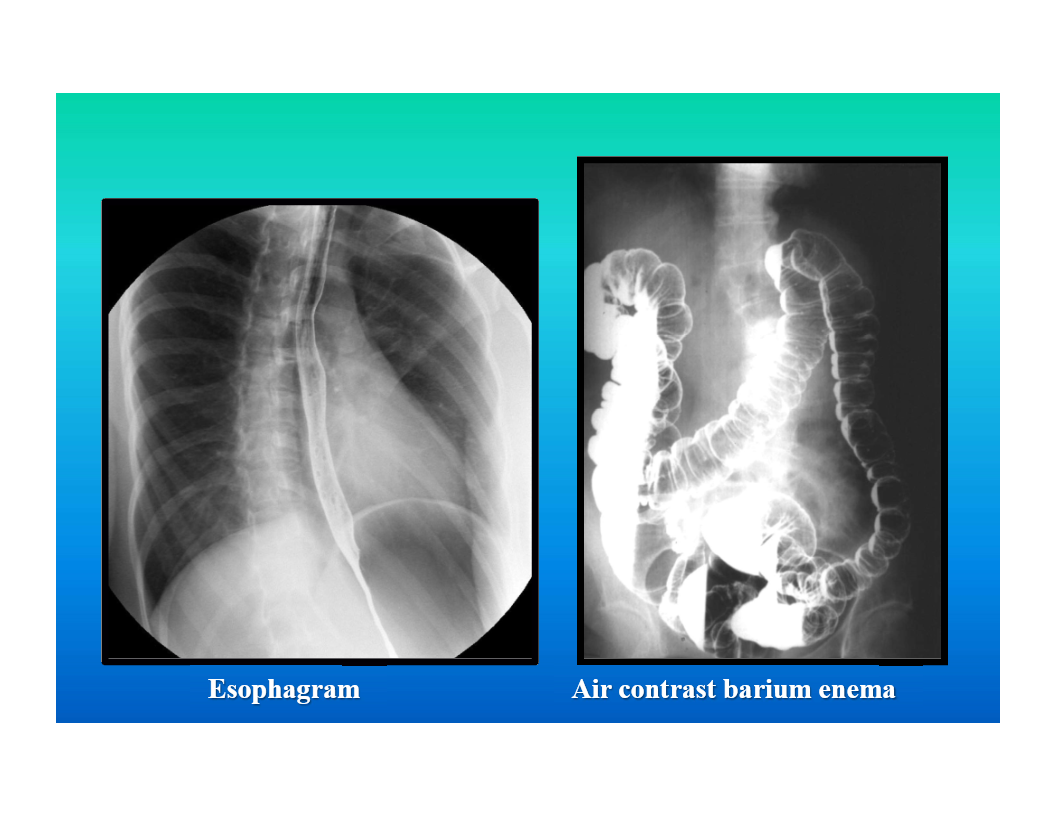

GI contrast studies

x-ray studies using barium or dilute water soluble iodine solution to evaluate GI tract

contrast administered orally to evaluate esophagus, stomach, and small bowel

contrast introduced via a rectal tuve for study of large colon

air contrast exams for mucosal detail

fluoroscopic monitoring